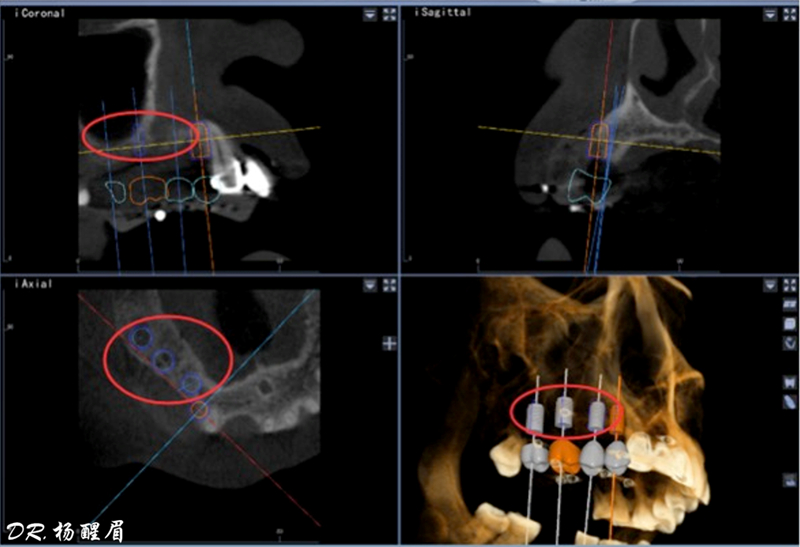

避免骨劈開及切牙管,這是由華西口腔的楊醒眉教授主刀的一次完美的前牙美學(xué)區(qū)數(shù)字化種植手術(shù)的病例!

此病例中主刀醫(yī)生借助迪凱爾數(shù)字化口腔種植手術(shù)導(dǎo)航系統(tǒng),精確的控制每鉆的定點精度和角度,保證了每次制備定點誤差小于0.4mm,角度偏差不大于3.5°,極大的保證了種植體按照種植前的手術(shù)設(shè)計就位。